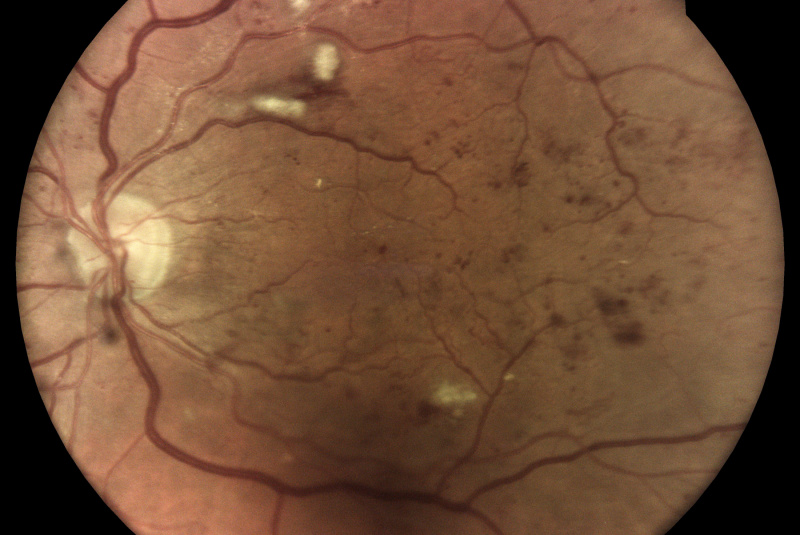

AI (umělá inteligence) okamžitě rozpozná práznaky diabetické retinopatie a klasifikuje výsledky podle závažnosti na základě mezinárodních klasifikací. Získáte přehled s hodnocením závažnosti záchytu, kde po analýze snímků zachycených kamerou iCare DRS Plus je automaticky generován report o pacientovi se stupnicí závažnosti pro diabetickou retinopatii na základě mezinárodních standardů (ICDR, AREDS).

Fundus kamera iCare DRSplus pořídí celkem 4 vysoce kvalitní True Color snímky (dva z pravého a dva z levého oka), které se automaticky ukládají na cloud a posílají se na zpracování AI - umělé inteligenci. Report je dostupný ihned a ten je možno konzultovat s pacientem během téže návštěvy u lékaře.